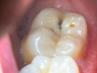

RIESGOS DE PADECER CARIES La higiene bucal es una de las más importantes, sin embargo a veces creemos que con lavarlos los dientes tres veces al dí¬a es más que suficiente para...